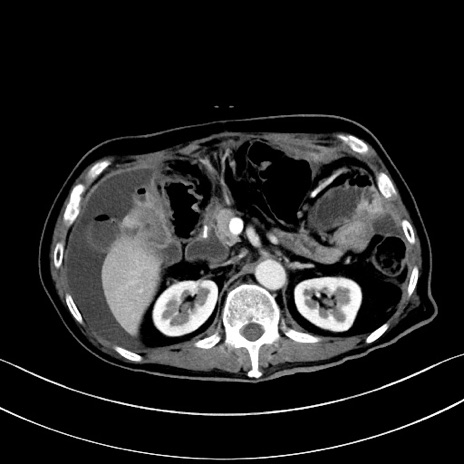

症例28(横断像)

【症例】60歳代男性

【主訴】嘔吐

【現病歴】胃癌にて胃全摘後。食思不振が悪化し、夜中に嘔吐することがある。

【既往歴】胃癌、胃全摘、脾摘、胆摘後

【データ】WBC 5900、CRP 10.56